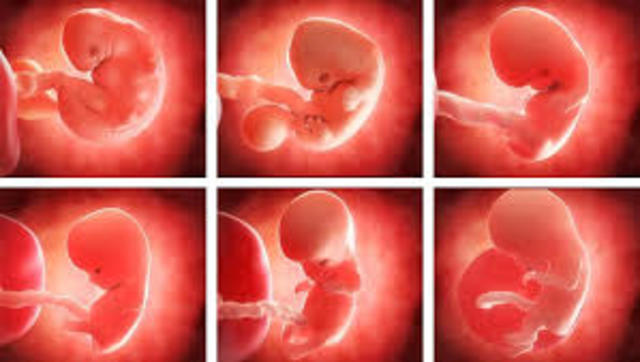

El cigoto se convierte en embrión. desarrolla el sistema circulatorio, el corazón y brotes de lo que posteriormente serán los brazos y piernas. presenta una cola que es el inicio del cordón umbilical. Se forman los dedos de las manos y pies, los labios, el hígado, orejas y ojos.

Las uñas empiezan a crecer y los huesos a endurecer, los riñones producen orina y los órganos sexuales empiezan a desarrollarse.

Comienza a crecer el cabello y los órganos sexuales interno se ubican en la posición de la cadera